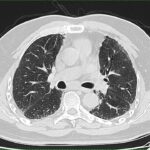

Você já ouviu falar sobre a Fibrose Pulmonar Idiopática? Acredito que a maioria das pessoas nunca tenha ouvido falar sobre essa doença. A Fibrose Pulmonar Idiopática é uma doença rara e grave, em que as células dos pulmões começam a cicatrizar de forma desconhecida. Isso faz com que as paredes das células fiquem mais rígidas e encolham, dificultando a respiração e levando a sintomas como cansaço e falta de ar.

Infelizmente, não conhecemos a causa dessa doença, mas sabemos quais são suas consequências. Pessoas com fibrose pulmonar podem ter uma limitação cada vez maior, ficando cada vez mais fracas e com fadiga. Alguns casos podem evoluir de forma muito rápida, levando à morte.